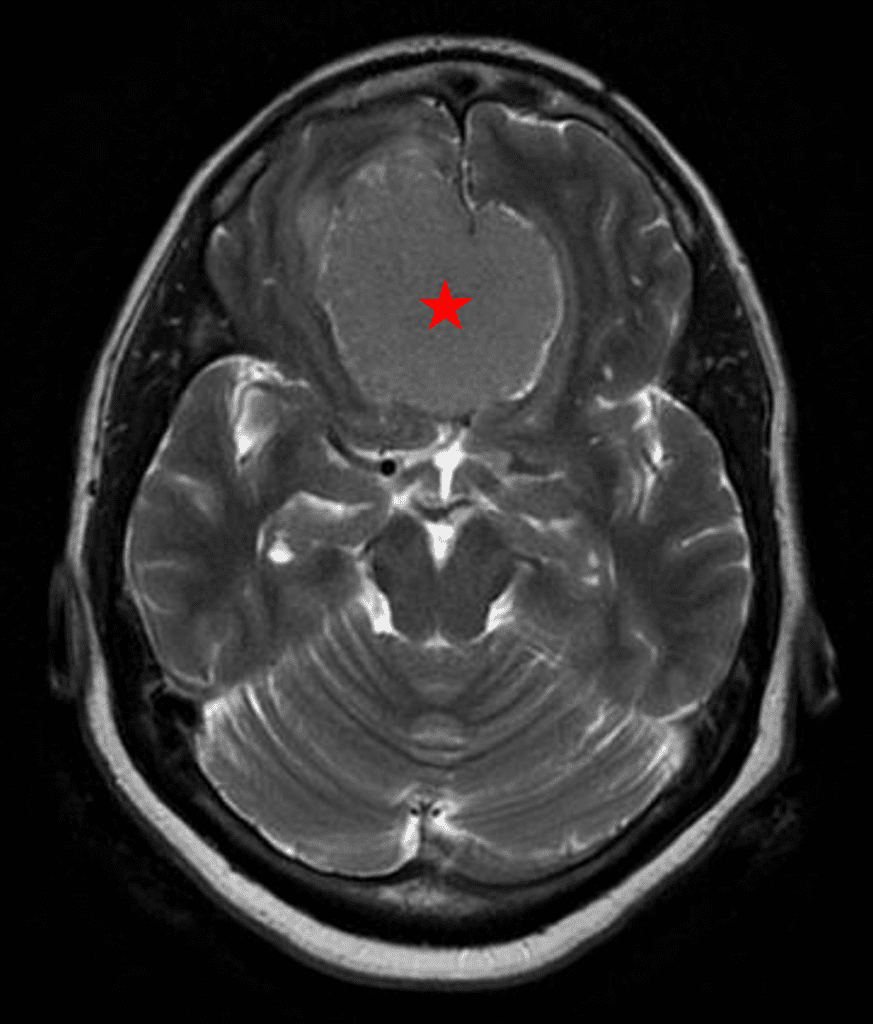

Figure 2a – Preoperative MRI demonstrating an extra-axial lesion with surrounding vasogenic edema and mass effect on the frontal lobes.

She was started on high-dose steroid and antiseizure prophylactic medicine. Surgical intervention was offered for mass effect, symptomatic relief, neurologic preservation, and histopathologic diagnosis. Dr. Gaudin performed a bifrontal craniotomy with complete resection of neoplasm through an interhemispheric and subfrontal approach. Postoperative imaging demonstrated a gross total resection without residual tumor and resolution of mass effect (Figure 1b and 2b). Intraoperative pathology was consistent with meningioma, WHO grade 1. She recovered very well, and was discharged home on postoperative day 3. On her follow-up outpatient visit, her preoperative symptoms had fully resolved, and her olfactory sense was maintained.

Figure 2b – Postoperative MRI demonstrating resolution of mass effect.